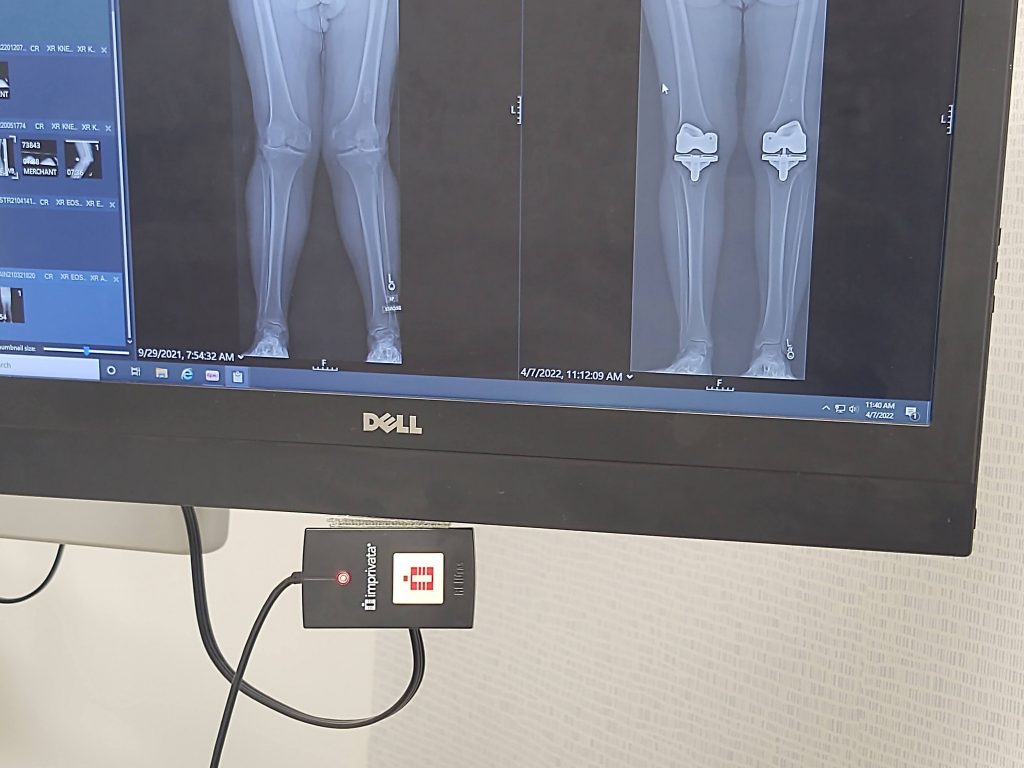

As you can see from the before picture, I was a mess! Bones bowed out, severe arthritis, no cartilage! Dr. J saw the photos and said he could help, but I wouldn't like him for about 4 to 6 weeks after surgery then my opinion would change. The left knee was done October 2021 and the right knee was done February 2022.

Now I do not think about standing up. I love walking and can go miles and stairs are no issue. I can walk the golf course and play other sports (as I am older I have no plan to play anything to cause undue torque and undo Dr. J's incredible work - if you are still an athlete, I know there is a more extensive PT regimen that could get you there). Most importantly, NO PAIN! Another great side effect is better posture and much less back pain. The picture shows how much more aligned my bones are from ankle to hip.